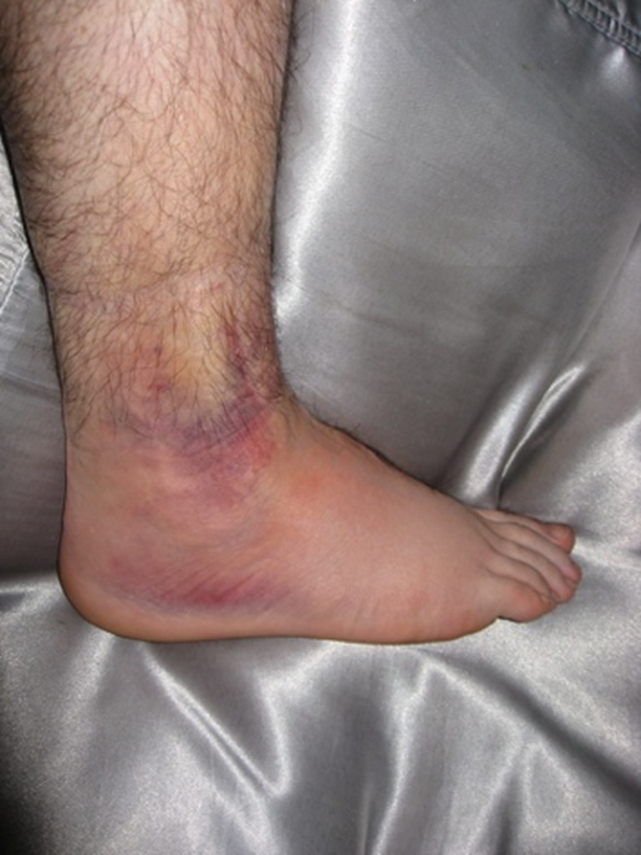

- Oedema and ecchymosis around the lateral aspect of the ankle

- Tenderness over the lateral ankle (both lateral malleolus and talus).

- Inability to weight-bear.